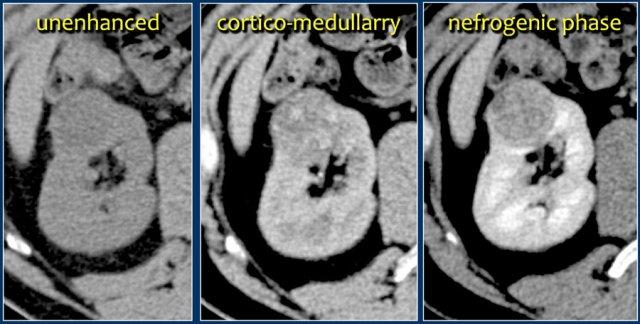

Quy trình chụp tối thiểu phải bao gồm thì không tiêm thuốc cản quang và thì thận (nephrogenic phase).

Thì vỏ-tủy (corticomedullary phase) từ 25-40 giây sau tiêm thuốc được khuyến cáo mạnh mẽ. Thì này giúp phân biệt khối u với giả u và đánh giá mức độ ngấm thuốc của tổn thương.

Tuy nhiên, trong thì này, một khối u nằm ở tủy thận có thể có cùng tỷ trọng với nhu mô xung quanh (hình minh họa).

Do đó, thì thận (±100 giây sau tiêm thuốc) là thì quan trọng nhất để phát hiện khối u.